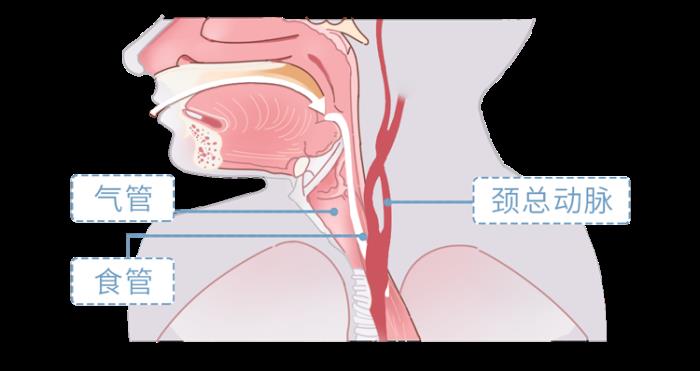

之所以喉结被摸时

会产生不适、不安全感

主要跟它的位置有关

喉结后面就是气管、食管

加上旁边还有人体的重要动脉

——颈动脉

这些重要且脆弱的部位

较为集中地分布在一起

一旦压迫到食管

可能会让人产生想吐的感觉

如果下手不知轻重

甚至可能压迫到气管

出现暂时窒息等状况